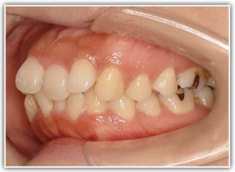

上顎前突ケース

治療法:表の矯正(T21ブラケット)

治療後(2年後)